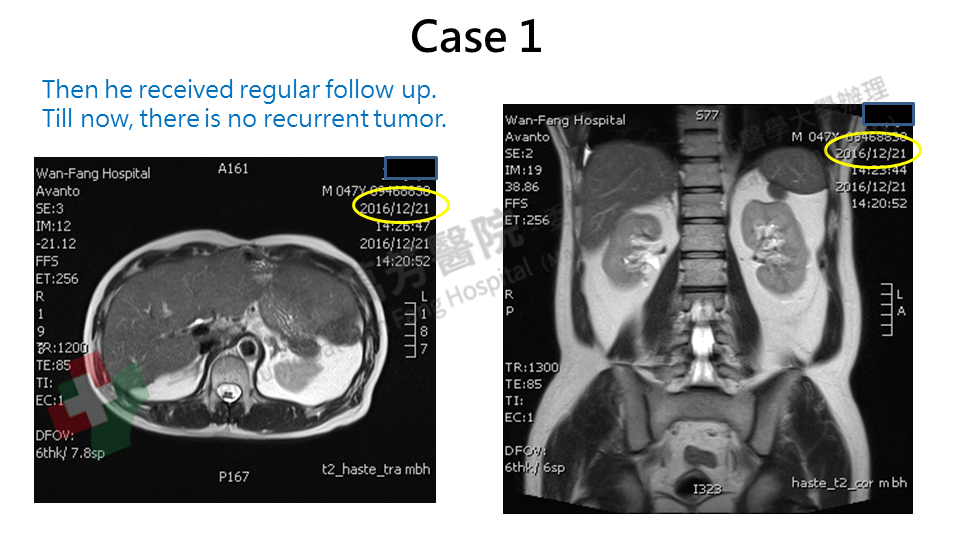

Case 1: A case of appendiceal mucinous adenocarcinoma. He received an operation for intestinal obstruction at other hospital. Only large amount of mucinous material was found without any tumor. Then he received the surgery for appendiceal cancer, peritonectomy and cytoreduction surgery with HIPEC on 2008. Local recurrence was found at follow up. Because surgical treatment was difficult, we arrange Cyberknife radiotherapy for him. At the present, he is still well without disease recurrence and returned to his regular work.